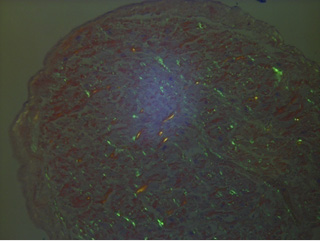

Несмотря на совершенствование неинвазивных методов диагностики «золотым стандартом», по-прежнему, остается биопсия миокарда. Морфологическое исследование с типированием амилоида в случае системного амилоидоза провести тактически легче. В качестве скрининга можно использовать биопсию подкожно-жировой клетчатки, а также исследование биоптатов ПЖК (информативны в 60–80% случаев), прямой кишки (50–70%), костного мозга (50–55%), кожи (50%), почки, печени, слюнных желез (90%). Морфологическое исследование препаратов костного мозга (полученных при трепанобиопсии) в совокупности с аспиратом подкожного абдоминального жира позволяет идентифицировать депозиты амилоида у 85% пациентов с AL-амилоидозом. Кроме того, исследование костного мозга дает возможность оценить размер плазмаклеточного клона и исключить ММ. Флуоресцентная гибридизация in situ (FISH) позволяет выявить мутации и, таким образом, оценить чувствительность клона к различным схемам противоопухолевой терапии [124–128]. Если подозрение АКМП обосновано, но скрининг не выявил амилоид, выполняется эндомиокардиальная биопсия. После обнаружения амилоида, окрашенного конго красным, с демонстрацией двойного лучепреломления в поляризующем свете и проведения окраски щелочным гуанидином по методу В.А. Варшавского или перманганатом калия для исключения АА-типа амилоидоза (при АА типе амилоида конгофилия и способность к анизотропии и дихроизму депозитов после инкубации в растворе перманганата калия исчезают)амилоид типируют. Для этого самым точным методом является лазерная микродиссекция в сочетании с масс-спектрометрией, которая позволяет идентифицировать все известные типы амилоида (протеомный анализ имеет специфичность 100% и чувствительность 90% [129]), но доступна она только в некоторых специализированных центрах. Поэтому в современных реалиях оптимально использовать иммуноэлектронную микроскопию с меченными золотом антителами (специфичность 100%) или иммуногистохимическое исследование с валидированными антителами, поскольку использование коммерческих антител может привести к неправильному диагнозу [130, 131].

На секции диагнозы хронической обструктивной болезни легких в стадии обострения и цереброваскулярной болезни были подтверждены. Выявлена гипертрофия левого желудочка с толщиной МЖП 1,5 см, свободной стенки ЛЖ 2,0 см. В препарате из правого предсердия (ПП) умеренный интерстициальный фиброз, очаговое утолщение и склеротические изменения в эндокарде. С учетом старческого возраста пациентки и наличия рецидивирующей формы ФП дополнительно были окрашены конго красным и исследованы в поляризованном свете препараты ПП, ЛЖ, толстой кишки, печени, селезенки и почки. В препарате с тканью ПП выявлены множественные мелкие диффузно-рассеянные депозиты амилоида в интерстиции, единичные очаговые микродепозиты в эндокарде и стенках артериол; в соотношении интерстициального фиброза и депозитов амилоида преобладал амилоид (рис. 4, 5). В препарате с тканью левого желудочка выявлен единичный мелкий депозит в интерстиции в субэндокардиальном отделе. В препаратах с другими образцами (толстая кишка, печень, селезенка и почка) депозитов амилоида не выявлено.

Рис. 5. Депозиты амилоида в предсердии. Окраска конго красный, поляризационная микроскопия. Ув. × 20.

Пациент А., 65 лет, длительное время страдавший гипертонической болезнью 3 ст., осложнившейся развитием ранее инфаркта миокарда, а также хроническим пиелонефритом, похудел на 30 кг в течение 3 месяцев, стали беспокоить тошнота и рвота. Затем появилась устойчивая гипотензия до 90/60 мм.рт.ст., наросли одышка, слабость, появилось сердцебиение, умеренные отеки нижних конечностей. На ЭКГ была выявлена блокада передней ветви левой ножки пучка Гиса, синусовая тахикардия. При суточном мониторировании ЭКГ по Холтеру эпизодов нарушений ритма не зарегистрировано. По результатам ЭхоКГ выявлена концентрическая гипертрофия миокарда ЛЖ до 1,6 см, E/A=0,5, КДО 78 мл, ФВ 57%. Также диагностирован окклюзионный тромбоз правой подколенной вены, назначен ривороксабан. Через 5 дней пациент был экстренно госпитализирован с направительным диагнозом «Кишечное кровотечение». При тотальной колоноскопии: множественные эрозии в толстом кишечнике, контактная кровоточивость, взята биопсия (рабочим диагнозом на тот момент был язвенный колит). Через 2 дня у пациента развился пароксизм ФП с ЧСС 181 в минуту, критической гипотензией до 58/15 мм рт. ст.; ритм восстановлен электрической кардиоверсией. Затем, через 2 суток, повторный пароксизм ФП, с гипотонией 82/52 мм рт. ст. Заподозрена легочная эмболия, не подтвержденная при компьютерной ангиографии. Через сутки пациент скончался вследствие электромеханической диссоциации. Одновременно было завершено морфологическое исследование кишечного биоптата, где были обнаружены массивные скопления аморфных мелких эозинофильных масс, с атрофией крипт, «замурованных» в гомогенных эозинофильных включениях, наличием поверхностных дефектов слизистой оболочки в зонах «растрескивания» данных включений. Мелкие узлоподобные конгломераты были также выявлены в стенках артериол слизистой оболочки и подслизистого слоя. При окрашивании конго красным – отчетливая конгофилия выявленных аморфных эозинофильных масс; при исследовании в поляризованном свете конгофильные включения демонстрируют способность к двойному лучепреломлению со свечением яблочно-зеленого и желтоватого цветов. По результатам пробы с перманганатом калия АА-тип амилоида отвергнут.